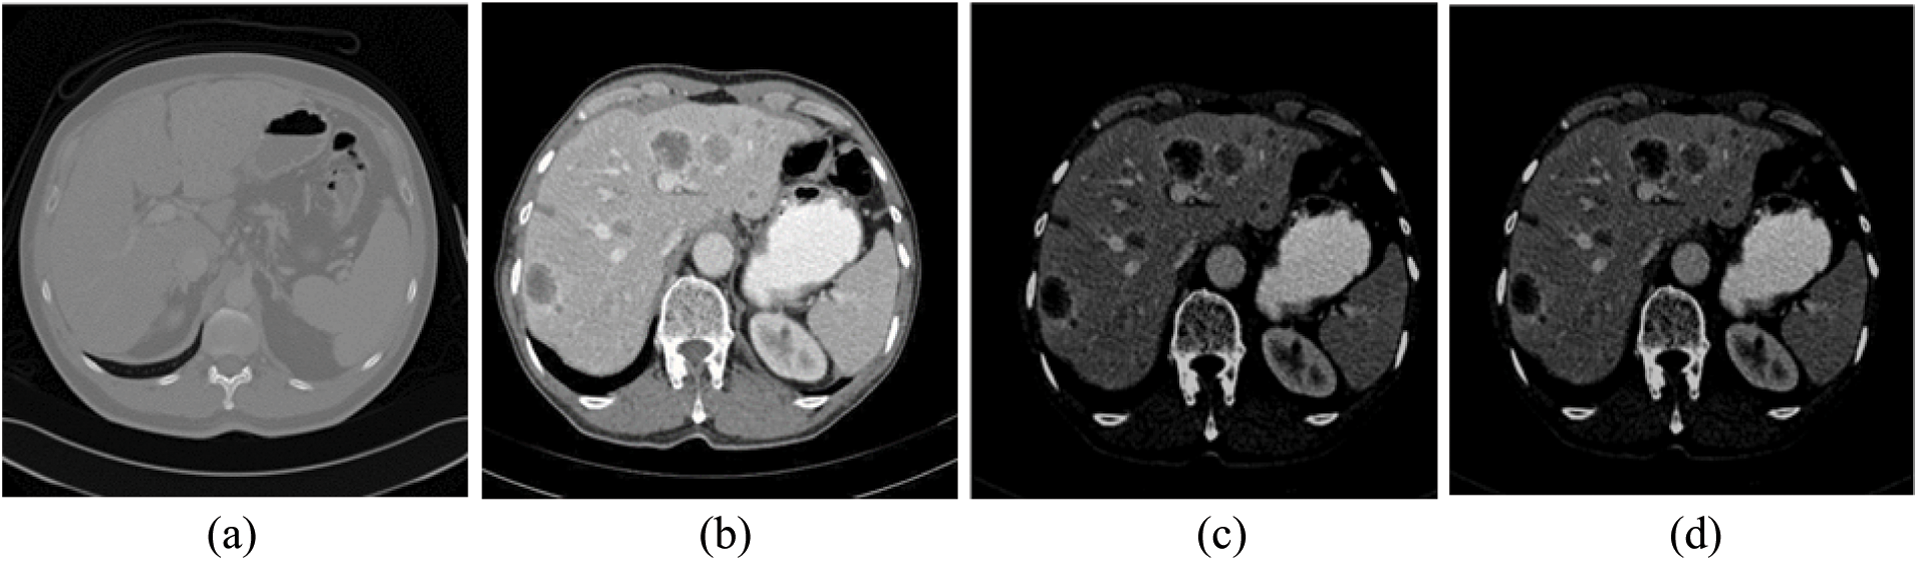

The impulse noise imposed by the CT scanner highly affects the segmentation process, since segmentation methods have high noise sensitivity. The proposed system reduced its effect using AMF method [38]. AMF detects pixels that were affected by impulse noise using spatial processing. AMF uses an adaptive window to label pixels as noisy pixels. It compares each pixel in the input image to its surrounding neighbor pixels in the window. An impulse noise-affected pixel has a different gray-level value than most of its neighbors and is not structurally aligned with the pixels to which it is similar. It replaces noise pixels values with the median value of their similar neighbor pixels and it has the advantage of preserving the edges and detailed information of the image. By the end of this stage, the CT scans are uniform, homogeneous and more suitable for the segmentation process (see Fig. 2).

Figure 2: The experimental results of the proposed method for steps 1–4 (a) Original CT scan, (b) Color mapped, (c) Contrast enhanced using AHE and (d) Filtered scan using AMF